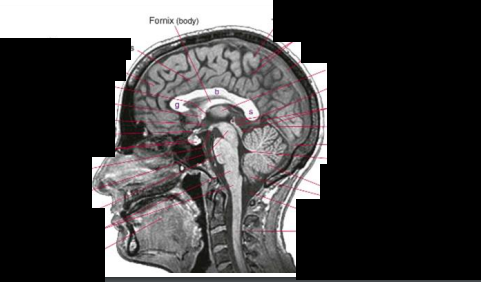

What structure in the brain is vital for fine motor control and is often connected to Parkinson’s?

Substantia Nigra